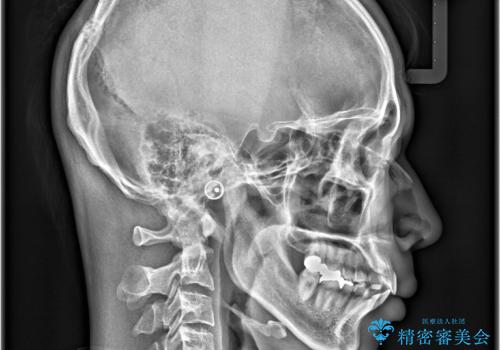

- 前歯の隙間と歯のデコボコを主訴にご来院された患者様です。

加えて、上下の奥歯が全く咬み合わないシザーズバイトの状態も認められました。

矯正検査の結果、非抜歯でインビザラインによる治療が可能と判断し、治療を行いました。